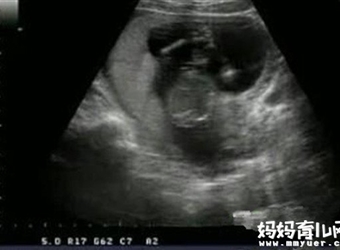

据说B超看胎儿性别是准确率比较高的一种方式,那么,怀孕四个月的时候可以通过B超查看胎儿性别吗?事实上,怀孕四个月的时候胎儿的生殖器官已经形成,此时正是…

胎儿五个月时性器官已经发育完善,你有没有好奇怀孕五个月男胎儿长什么样呢?如果你对此感兴趣,不如一起来看看怀孕五个月男胎儿图长啥样。

怀孕三个月的胎儿性器官已经慢慢发育成型,所以,这个时候利用B超来看男女是再合适不过的时间了。怀孕三个月男胎儿图什么样?怀孕三个月是男是女B超显示上有何…